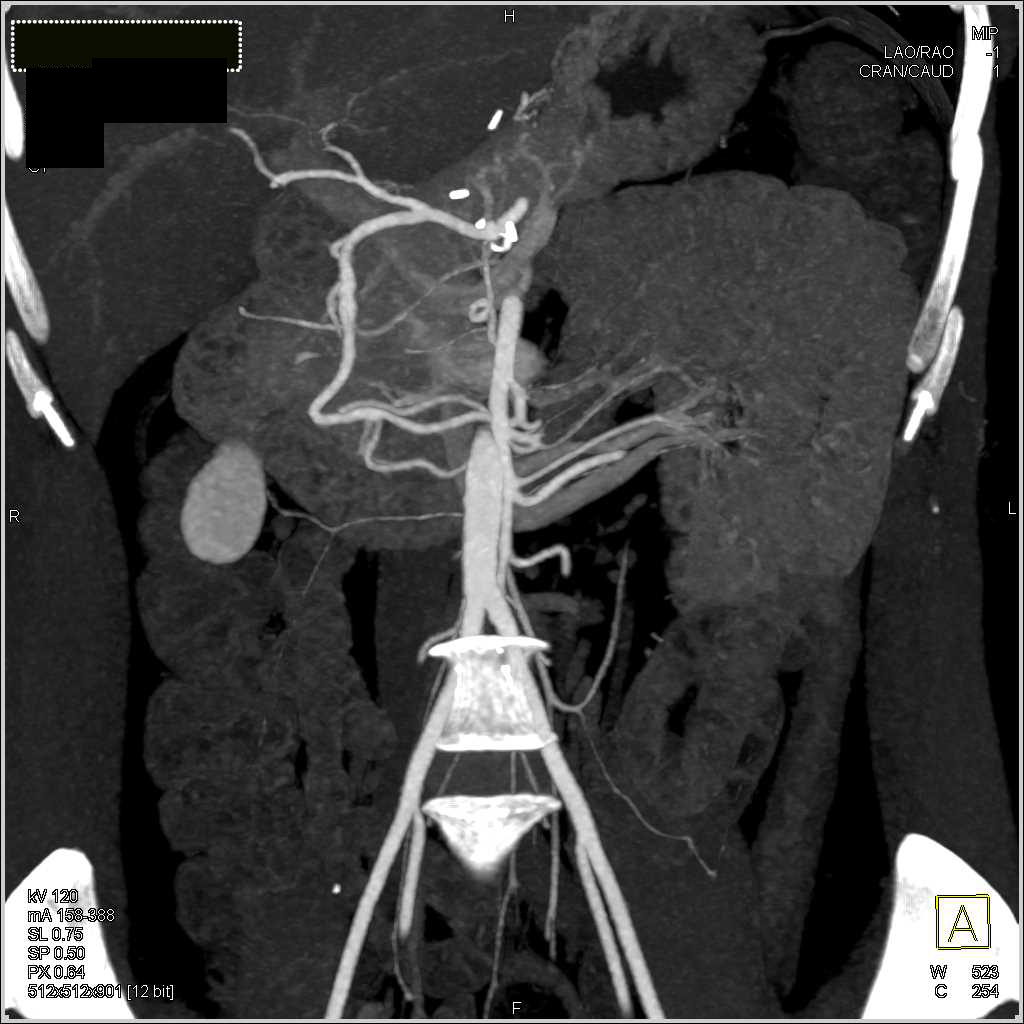

Normal Vascular Anatomy Especially Renal Artery and Veins